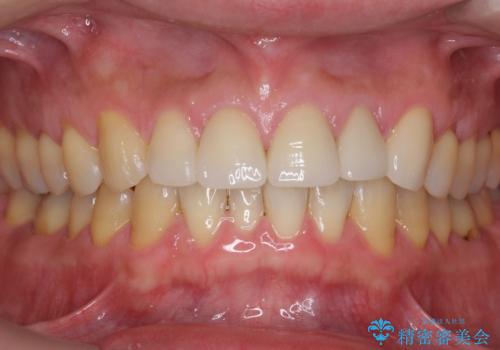

根の治療を行い、ぐらつきに関しては様子を見て連結をするとのお話をさせていただきました。

結果ナイトガードの使用によりぐらつきはだいぶ回復してきたため連結はしていません。

- 81.4万円 内訳:ジルコニアクラウン(スタンダード)11万円×4本 /精密根管治療 前歯、イニシャル 6万円×3本 /ファイバーコア 2万円×3本 /仮歯 1万円×3本/フラットタイプナイトガード 3万円費用は治療当時の料金となります